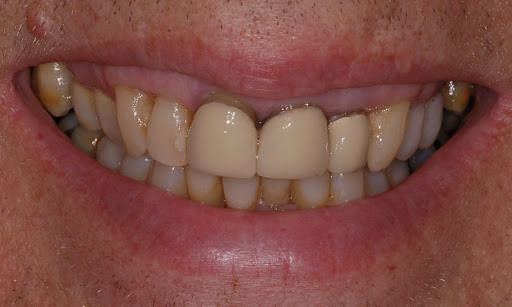

What Causes The Dark Line On My Gums?

You have seen smiles that you know have dental crowns in the front. You look at them and say to yourself that something is not natural. Many times, it is the dark rim of gum tissue that gives it away. The dark rim of gum tissue does not occur around natural teeth, only around teeth that have been covered with dental crowns.

The dark line is associated with an old porcelain dental crown. This style of dental crown is referred to as a porcelain fused-to-metal dental crown because it uses tooth-colored porcelain on the outside and it uses metal under the porcelain for strength. The dark line originates from the edge of the dental crowns where the porcelain and the metal meet at a knife-edge at the gum line. At the knife-edge, a very thin amount of the metal always shows. One of the illusionary techniques cosmetic dentists have used was to hide the thin dark line under the gum line. Over time, the gum tissue would recede and expose the dark line. In some patients the dark line would show through the gum and make it appear dark as well.

How Do You Get Rid of It?

The only way to eliminate the esthetic problem is to replace the dental crowns. When replacing just one single dental crown in the front, you should expect that it might take more than one try-in of the new dental crown before it is permanently cemented into place. Because your central incisors are the most prominent teeth in the mouth, matching them is the most difficult esthetic challenge. Only the best dental technicians are able to mimic one central incisor tooth next to another.

What Are Some of the Replacement Dental Crowns Like?

Some of the clever ways dentists and dental technicians have been able to mimic natural teeth is through the new advancements in dental materials. New all-tooth-colored ceramic dental crowns are the latest technological advancement cosmetic dentists have to recreate natural teeth. In comparison to porcelain fused-to-metal dental crowns, all-ceramic dental crowns do not contain any metal, thus no dark line can appear.

Some advantages and disadvantages of all-ceramic dental crowns are as follows:

Advantages of All-Ceramic Dental Crowns

High esthetics

Excellent fit

If gum recession occurs, there is no dark line

Disadvantages of All-Ceramic Dental Crowns

Not as strong as porcelain-fused-to-metal dental crowns

Cannot be used in all areas of the mouth.